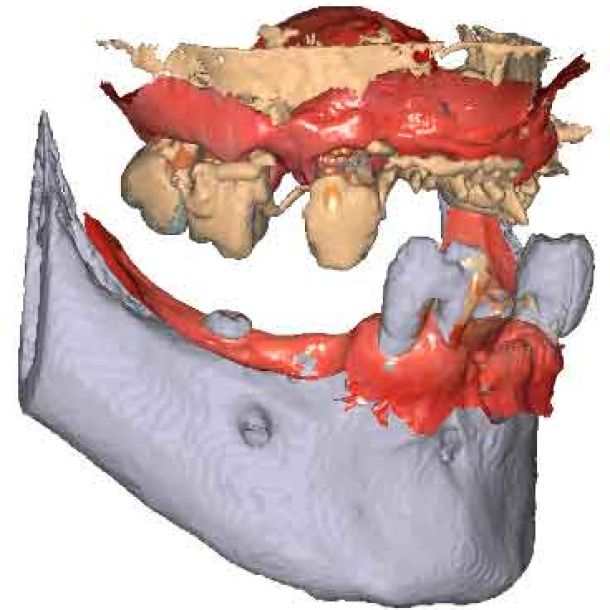

étape 2 – Acquisition du CBCT

Lorsque les scans IOS traditionnels manquent de références nécessaires, les données du CBCT peuvent servir d'alternative viable. En utilisant les fichiers du CBCT, le clinicien peut établir des références anatomiques précises pour la planification du traitement.

Pour pouvoir utiliser les données CBCT comme modèles initiaux, nous devons transformer le fichier DICOM en un fichier STL. Découvrez-en plus sur la segmentation CBCT et son utilisation dans TWIM ci-dessous.

Avant d'acquérir le CBCT, j'ai ajouté 2 morceaux de composite à la mandibule pour pouvoir effectuer le processus de picking pendant le protocole MODJAW. Il s'agit d'une astuce utile à retenir en cas d'absence de dents.

En important les fichiers DICOM du patient au lieu des scans IOS, les cliniciens peuvent enregistrer le mouvement de la mâchoire, facilitant ainsi la planification précise du traitement.

Importez les modèles CBCT segmentés en tant que modèles initiaux dans TWIM

Sélectionnez 4 points virtuels sur la mandibule du modèle osseux importé